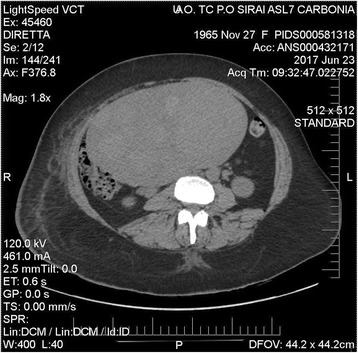

Fig. 2.

Case 2: axial computed tomography scan of the abdomen showing a huge inhomogenous uterus measuring more than 20 cm occupying entirely the right side of the pelvis